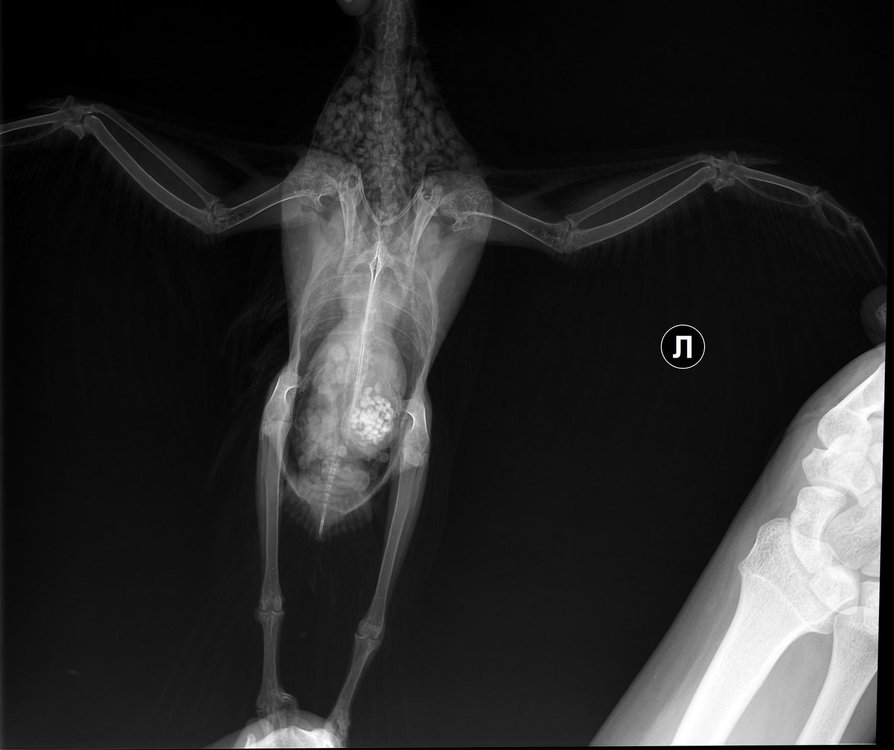

Очень нужен хороший хирург, который бы взялся за эту операцию по перелому бедра.

Оказалось, что переломы действительно неоперабельны (как и написала нам Zosia). Но и поводов для усыпления это, оказывается, не дает, вопреки мнению первого врача, у которого наблюдались.

Прошли мы конечно через многое: и с лапой беда, и двухсторонняя разлитая пневмония. И, плюс ко всему, когда отек тканей спал, оказалось, что еще и позвоночник был поврежден рядом со сломанным бедром (на 1м рентгене из-за отека не было видно). Вообщем прошли мы с Тосей огонь, воду и медные трубы. Вопрос об усыплении стоял несколько раз, но подруга наша сдаваться не собиралась.

Теперь победили пневмонию, позвоночник наш зажил на отлично, как показал последний рентген. Осталось разобраться с ногой: есть маленькая надежда, что все-таки будет хотя бы опираться на нее. В любом случае будем просто хромать или прыгать, покажет время. Главное, что жить будем и болевой синдром сходит на нет. Тося (судя по рентгену, девочка) у нас просто потрясающая: не знала, что гульки могут быть такими умными и послушными. Быстро привыкла к нам и уже не боится, не смотря на то, что мучаем ее лекарствами по 6 раз в день. Теперь будем думать, как обеспечить ей счастливую жизнь в квартирных условиях... чую, это будет не просто...